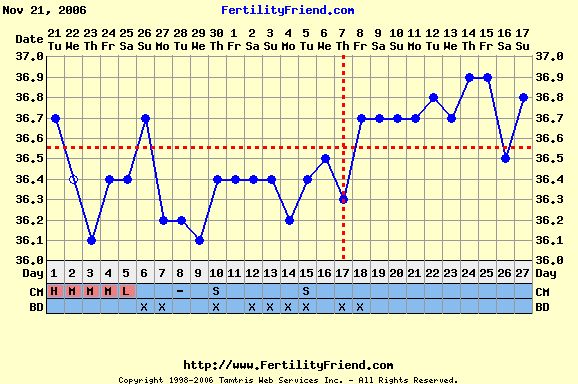

Verzsike, szerintem ebből a görbéből még akármi lehet. A legjobb egy + volna a tesztek sávjában!

Ez a leesés akár beágyazódás is lehetett!!!